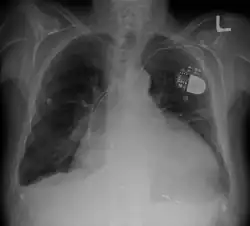

Devices to regulate heartbeat

- Pacemaker: Coordinates contractions between ventricles. In people at risk of arrhythmias, drug therapy or an implantable cardioverter-defibrillator (ICD).

- ICDs: Small devices implanted in the chest to monitor heart rhythm and deliver electrical shocks to control abnormal heartbeats. The devices can also work as pacemakers.